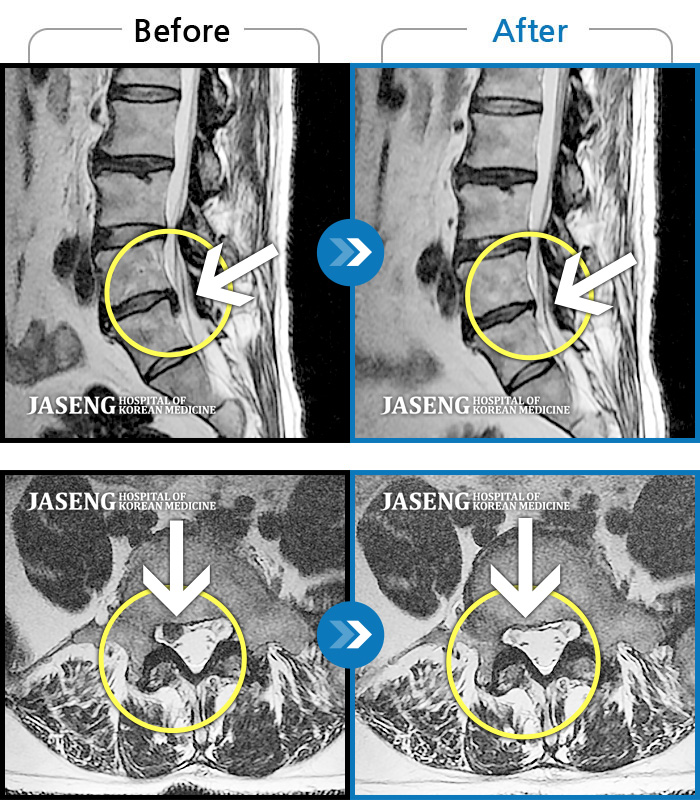

Before

After

환자에게 사전 동의를 받아 동일 조건에서 촬영되었습니다.

개인에 따라 치료 후 부작용이 발생할 수 있으니 의료진과 상담 후 치료를 진행하시기 바랍니다.

허리와 골반 통증, 누워서 다리를 움직일 때 통증 발생

허리통증, 왼쪽 다리 통증 및 근력 저하